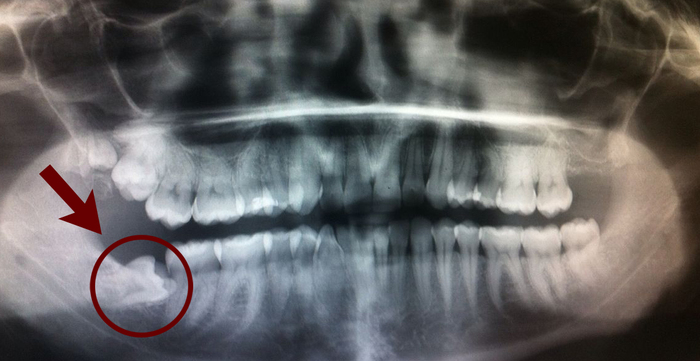

Оказалось режется зуб мудрости, причем криво и необходимо его ликвидировать

Но как в процессе лечения вырывать зуб??? Не просто так же в рекомендациях сказано, что нужно полоскать рот три раза в день после каждого приема пищи для предотвращения стоматита. Сейчас с заживлением ран итак все туго и создавать лишнюю пропасть в ротовой полости для сбора инфекции не хотелось бы…